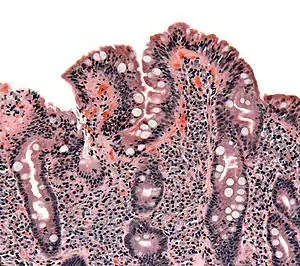

| Biopsy of small bowel showing coeliac disease manifested by blunting of villi, crypt hyperplasia, and lymphocyte infiltration of crypts | |